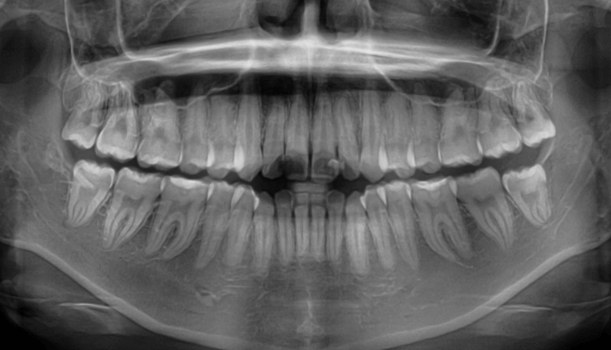

| 年齢・性別 | 15歳の女性 |

|---|---|

| 主訴 | 咬み合わせが逆であること(反対咬合)を気にされて来院された15歳7か月の女性。見た目や機能面の改善を希望されていました。 |

| 治療期間・回数 | 4年4ヶ月・28回 |

| 費用 | 900,000円 |